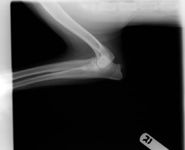

Photo 1: A "clean" lateral elbow radiograph of a dog with TFMCP.

Further diagnostic tests to help differentiate causes of elbow pathology include arthrocentesis, imaging and arthroscopy. Radiographs are of little value in identifying the fragment or line of separation seen with classic FMCP or TFMCP (Photo 1). More advanced imaging techniques such as computed tomography, magnetic resonance imaging and arthroscopy may help confirm the condition. Arthroscopic evaluation of the elbow joint has the advantages of direct observation and magnification of all principal intra-articular structures, dynamic evaluation of tissues during range-of-motion exercises and palpation of intra-articular tissues with arthroscopic instruments. Consequently, arthroscopic exploration can help definitively diagnose TFMCP when a fragment or cartilage fissure is observed (Photo 2). In a small percentage of cases, advanced imaging (computed tomography, magnetic resonance imaging) indicates fragmentation of the coronoid not seen with arthroscopy. In such cases, the microcracks are thought to be within the coronoid bone beneath the cartilage surface.